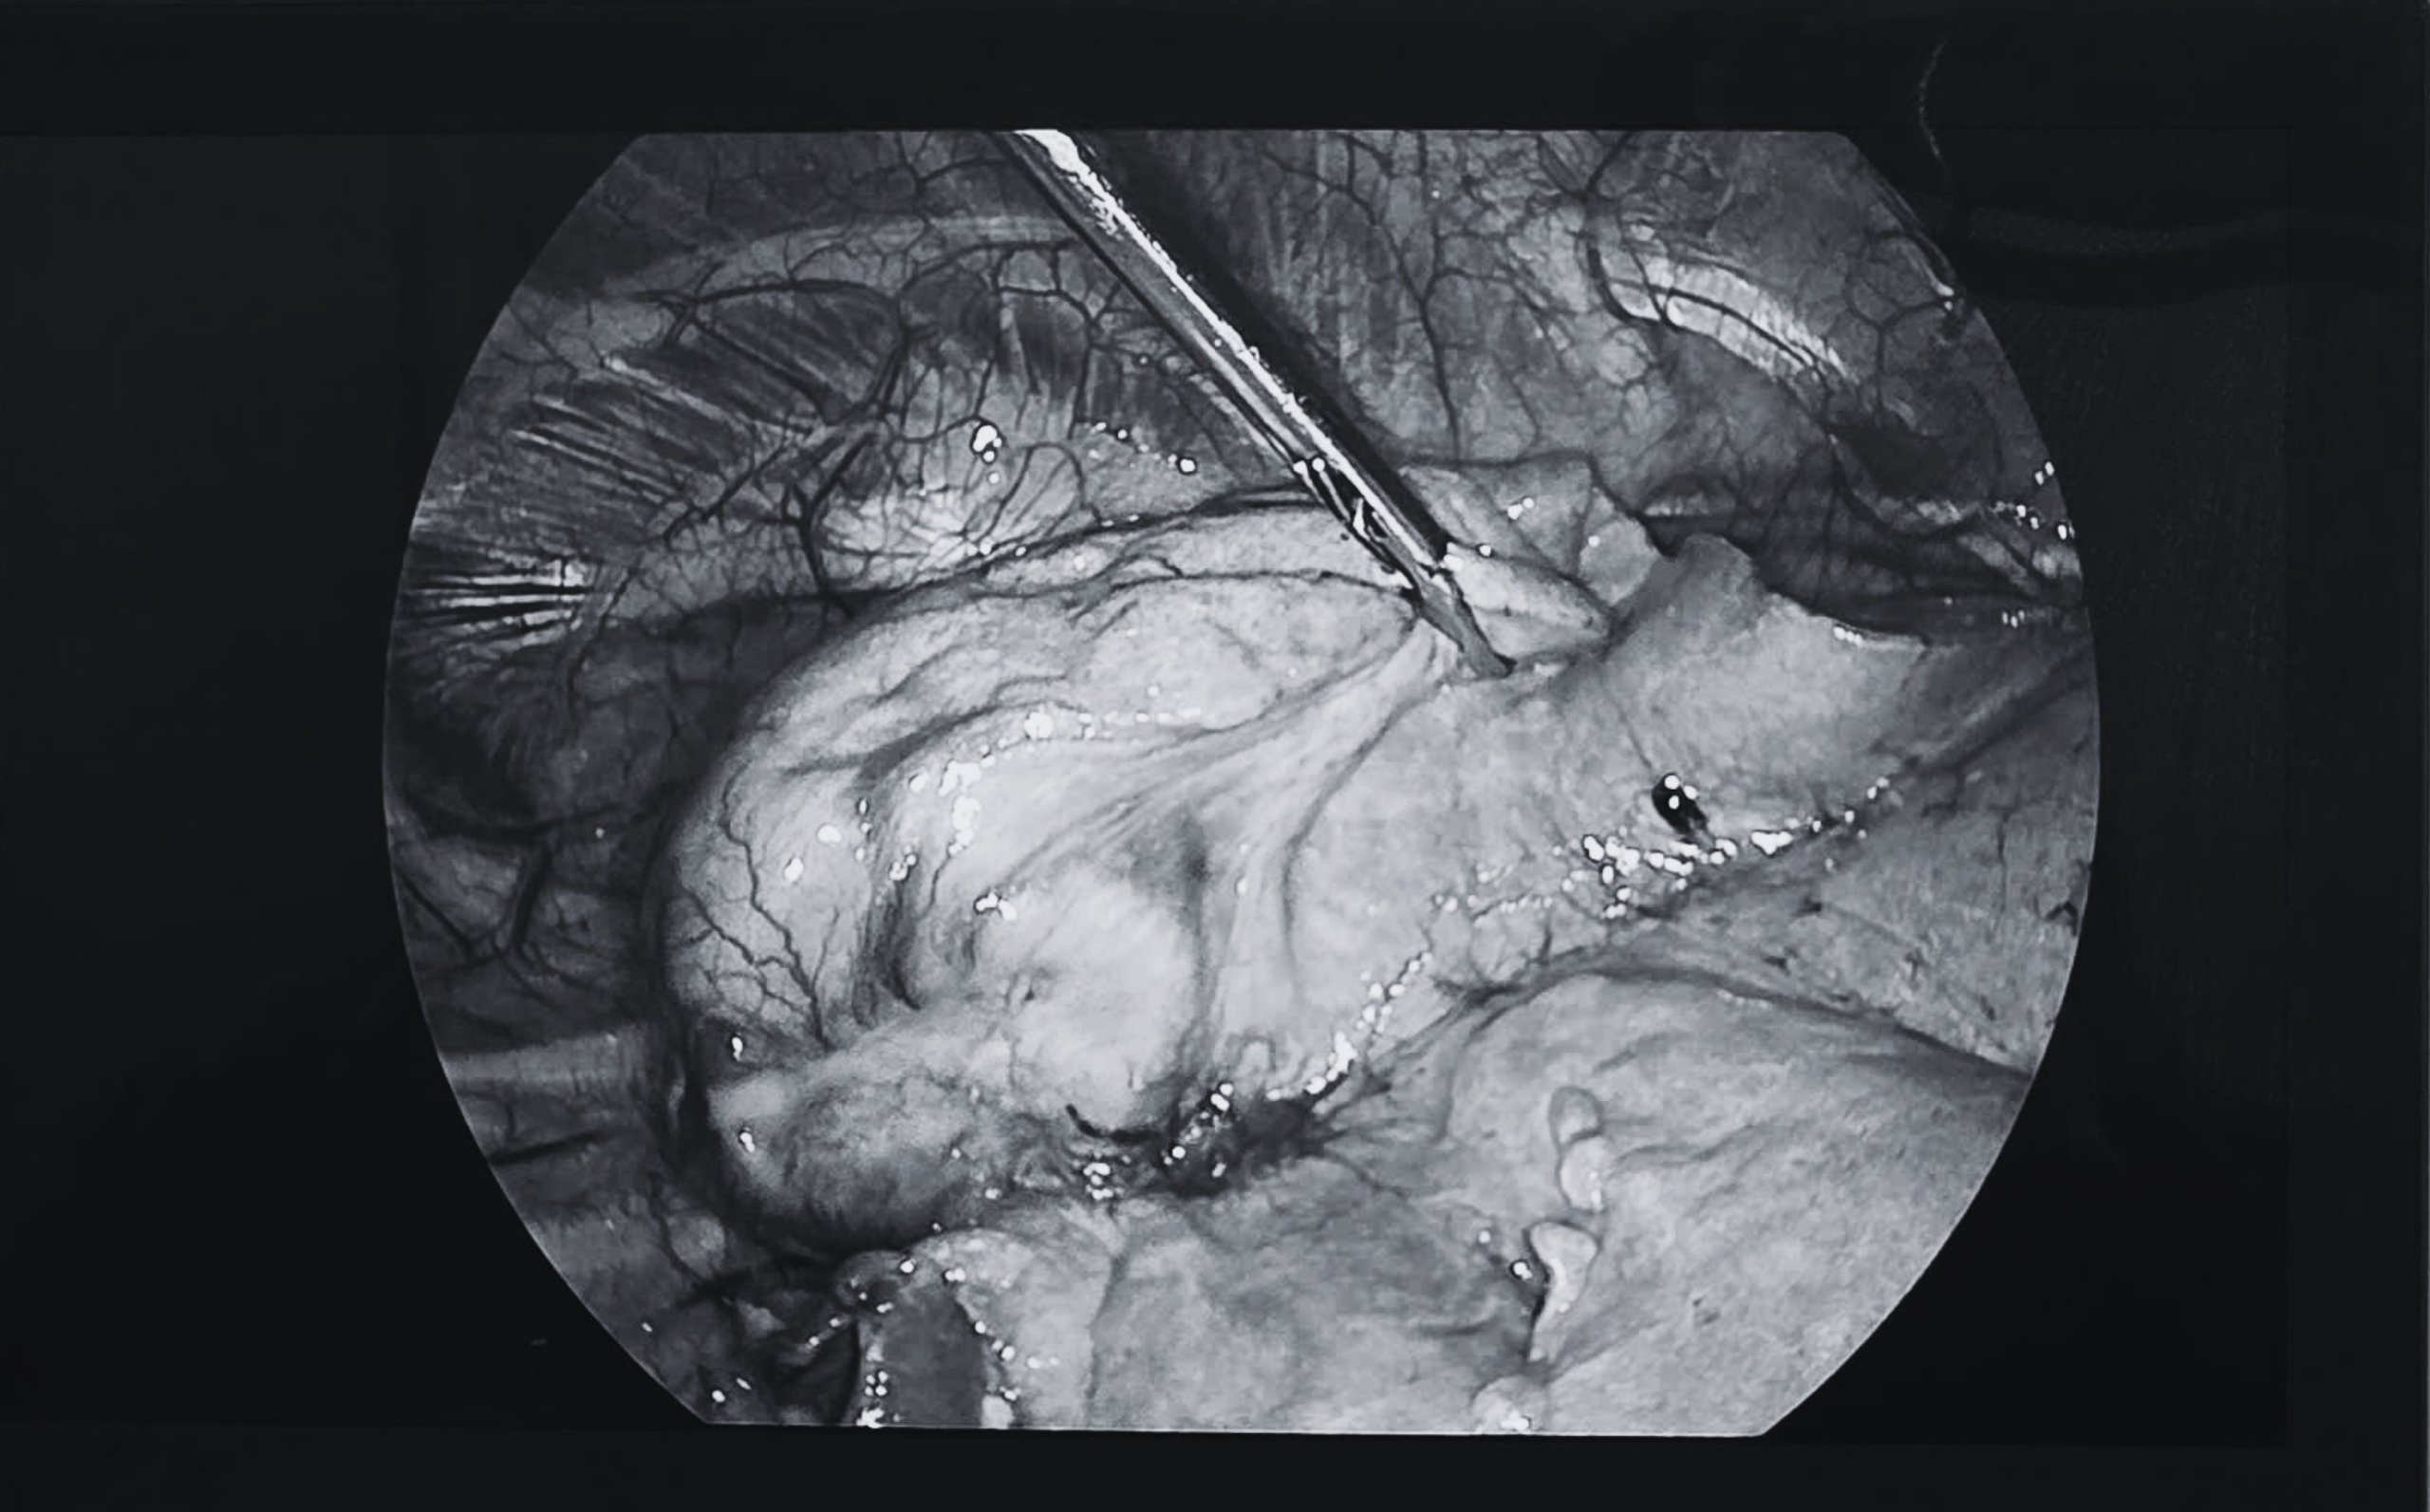

Ngay lập tức, ca phẫu thuật nội soi lồng ngực được chỉ định. Ê kíp phẫu thuật gồm Phó giáo sư - tiến sĩ - bác sĩ Vũ Hữu Vĩnh, bác sĩ chuyên khoa 1 Phạm Phú Khang (cựu bác sĩ nội trú), phối hợp cùng đội ngũ gây mê hồi sức, đã tiến hành thăm dò và phát hiện khối u tại phân thùy S2 có kích thước khoảng 4×3 cm, rắn chắc và co kéo nhu mô phổi.

Bằng kỹ thuật khâu cắt nối nội soi hiện đại, các bác sĩ đã cắt trọn phân thùy phổi chứa khối u, đồng thời nạo hạch số 7, 10 và 11. Toàn bộ ca phẫu thuật diễn ra thuận lợi và kết thúc trong 3 tiếng, mẫu bệnh phẩm được gửi giải phẫu bệnh thường quy nhằm xác định bản chất của khối u.

Khối u phổi được bóc tách qua kỹ thuật phẫu thuật nội soi lồng ngực